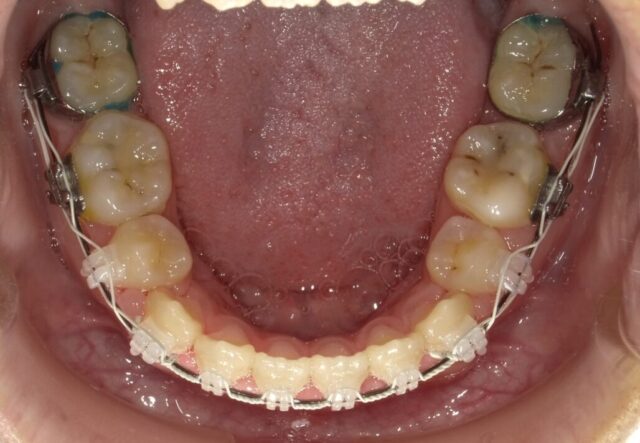

≪下顎咬合面観≫

2023年5月